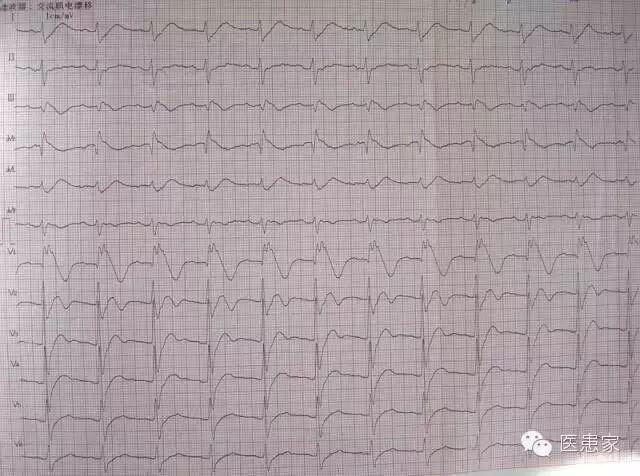

宽QRS心动过速

室 速